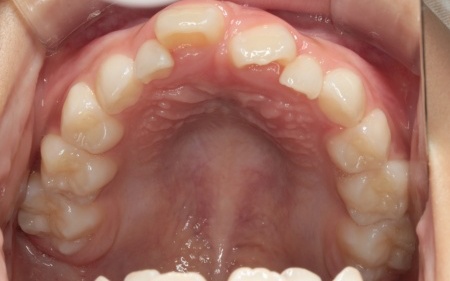

10歳女の子 顎の幅を広げる装置とマウスピース型の矯正装置で反対咬合を改善した症例

拝見したところ、上前歯が下前歯の内側に入り込む「反対咬合(こうごう)」が認められました。

詳しい検査の結果、患者様の反対咬合は歯の位置の問題ではなく、上顎の発育が十分ではないことが主な原因と考えられます。

まずは、「バイオブロック」による治療で上顎の発育を促すこと、その後、前歯の位置を細かく整えるためマウスピース型矯正装置「インビザラインファースト」と、上顎を前方へ引き出す「前方牽引装置」を併用する治療計画を提案しました。